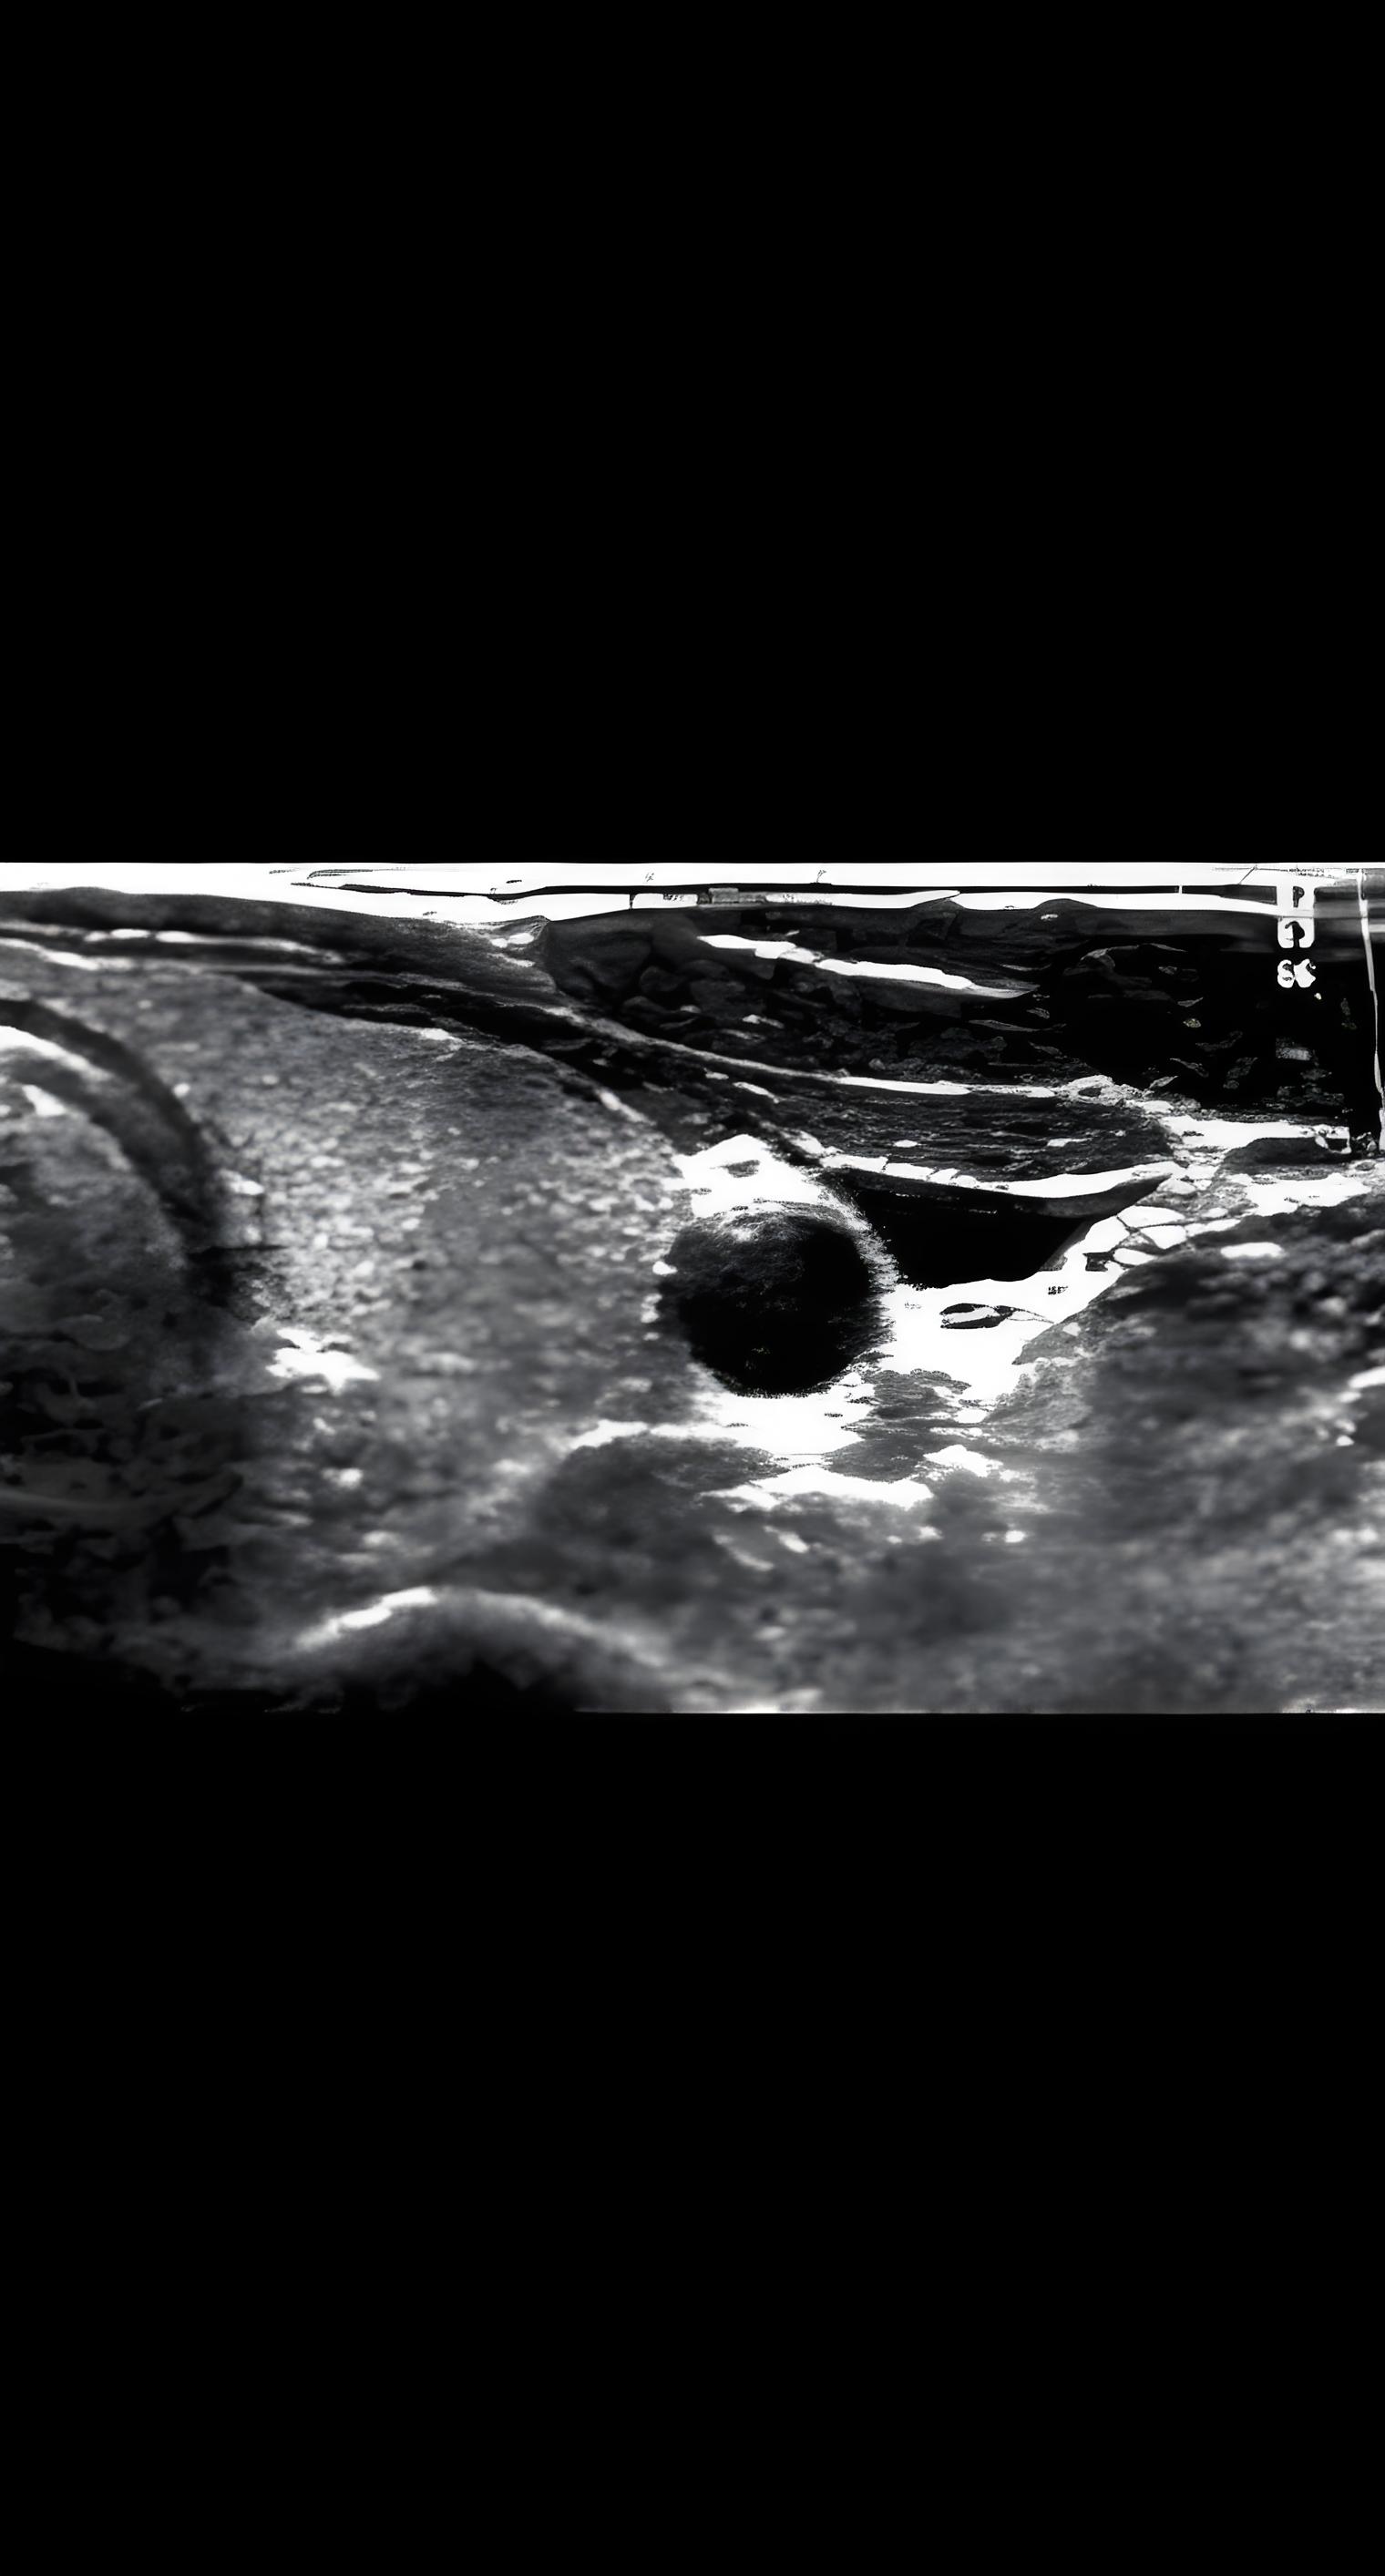

甲状腺结节多个医院超声结果,21年10月份体